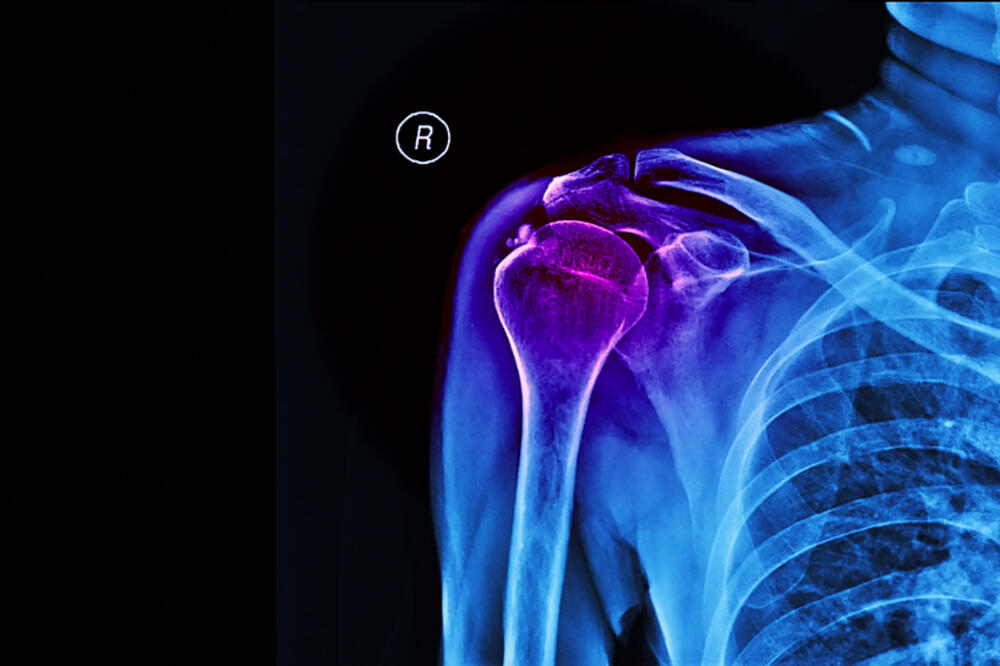

Шта је калцификација и зашто је опасна: Страдају артерије, бубрези…

Калцијум је један од најзаступљенијих минерала у тијелу. Има га свуда: у костима, зубима, па... The post Шта је калцификација и зашто је опасна: Страдају артерије, бубрези… appeared first on ИН4С .